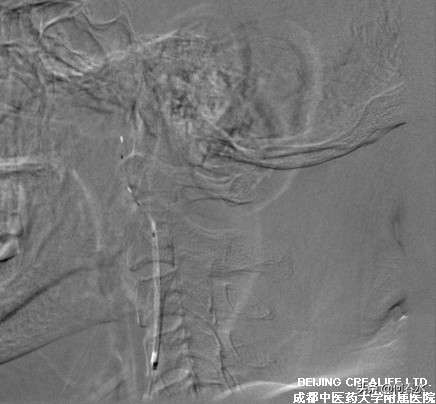

入院后完善相关检查,全脑血管造影示:两侧颈内动脉起始部重度狭窄,以左侧尤甚,左侧颈外动脉起始处1cm管腔向心性狭窄,程度80%。右侧颈总动脉末端管腔不规则轻度狭窄,右颈内动脉起始处2cm管腔狭窄60%,同侧颈外动脉起始处狭窄50%,远端右侧大脑前、大脑中动脉显示未见异常,左侧大脑前动脉借前交通动脉由右侧颈内动脉供血。

相关术前准备后,于2015年4月27日行手术治疗:患者仰卧位,心电监护,吸氧,麻醉师控制血压在130mmHg左右,尼莫同2.5ml/小时持续泵人,麻醉后穿刺右股动脉,引入8F鞘,并以Telescope技术(同轴法)引入5F/125cm椎动脉导管及8F MPA1指引导管在左颈总动脉远端,然后在路图下,送入0.014导丝,通过左颈内动脉近端狭窄段,然后以快速交换方式沿导丝引入保护伞至狭窄段远端,并张开伞。然后沿保护伞导丝送入4mm*15mm Quantum Maverick Monorail快速交换球囊,以压力泵预扩张至球囊内压16ATM后迅速释放球囊,然后沿导丝送入8mm-6mm*40mm Protégé锥形支架,定位后准确释放,造影复查见颈内动脉闭塞段开通满意,支架位置良好,颅内血流增加,原未显示的左侧大脑前动脉充盈满意。手术顺利,病人安返。

图片说明:造影显示,颈内动脉起始段重度狭窄,狭窄率达95%